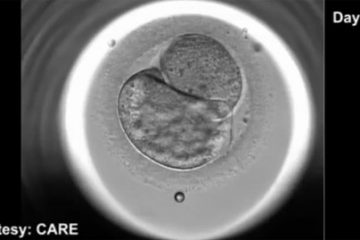

Cha mẹ có thể chứng kiến giây phút con được thụ thai

Với một loại kính hiển vi mới, các bác sĩ sản khoa có thể quan sát được quá trình hình thành và phát triển của phôi liên tục trong ...